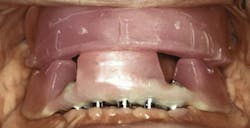

Where is the smile line in relation to the display of natural tissue within the smile? Evaluation of the smile line will determine if you need pink tissue built into the restoration or whether you will need to prescribe a bone reduction as part of the surgical procedure. Mark the lip line on the bite block to identify the tooth display in the smile (figure 4).

Figure 4: Mark the position of the upper lip line on the implant bite block when the patient is smiling.